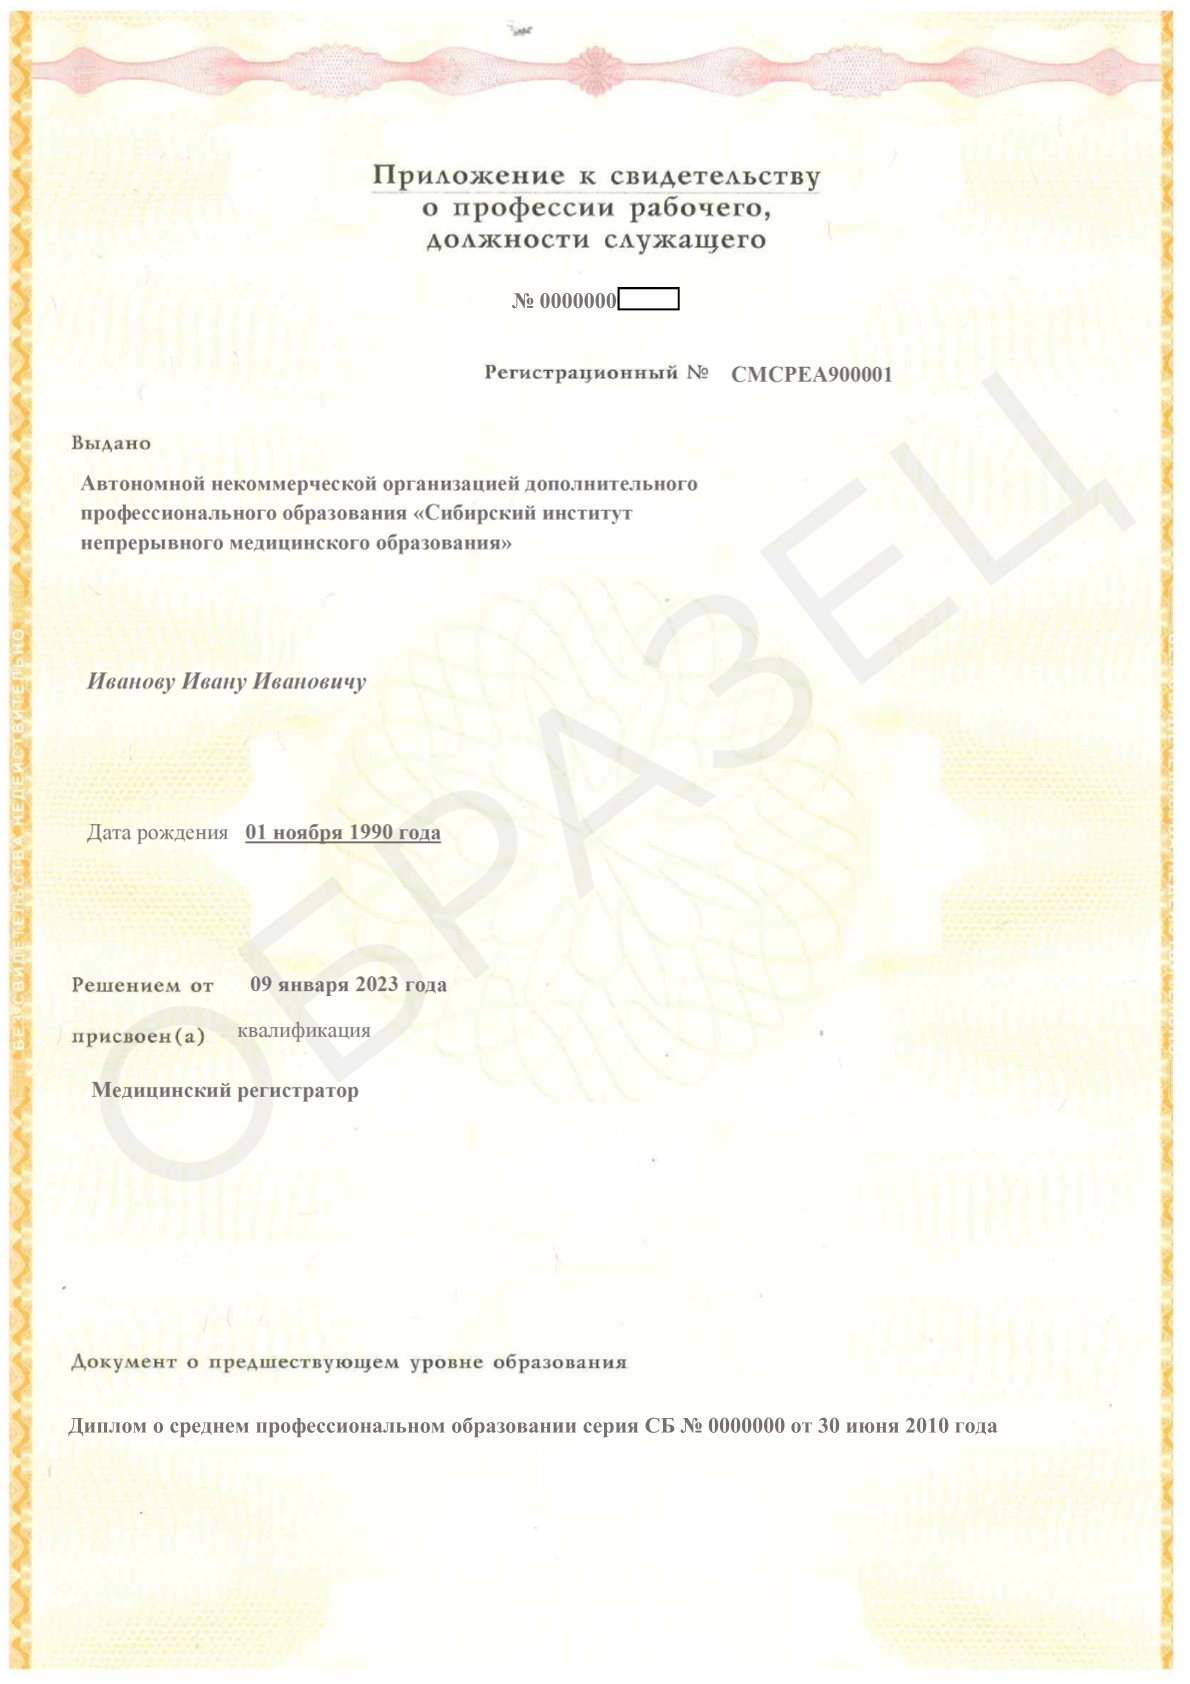

Смотреть документ

Смотреть документ